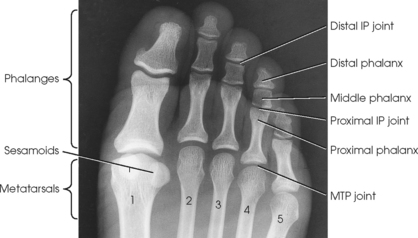

The foot consists of 26 bones (Figs. 6-1 and 6-2):

Each foot has 14 phalanges—2 in the great toe and 3 in each of the other toes. The phalanges of the great toe are termed the distal and proximal phalanges. The phalanges of the other toes are termed the proximal, middle, and distal phalanges. Each phalanx is composed of a body and two expanded articular ends—the proximal base and the distal head.

The five metatarsals are numbered one to five beginning at the medial or great toe side of the foot. The metatarsals consist of a body and two articular ends. The expanded proximal end is called the base, and the small, rounded distal end is termed the head. The five heads form the “ball” of the foot. The first metatarsal is the shortest and thickest. The second metatarsal is the longest. The base of the fifth metatarsal contains a prominent tuberosity, which is a common site of fractures.

The proximal foot contains seven tarsals (see Fig. 6-1):

Beginning at the medial side of the foot, the cuneiforms are described as medial, intermediate, and lateral.

The cuboid bone lies on the lateral side of the foot between the calcaneus and the fourth and fifth metatarsals (see Fig. 6-1). The navicular bone lies on the medial side of the foot between the talus and the three cuneiforms. The cuneiforms lie at the central and medial aspect of the foot between the navicular bone and the first, second, and third metatarsals. The medial cuneiform is the largest of the three cuneiform bones, and the intermediate cuneiform is the smallest.

The interphalangeal (IP) articulations, between the phalanges, are synovial hinges that allow only flexion and extension. The joints between the distal and middle phalanges are the distal interphalangeal (DIP) joints. Articulations between the middle and proximal phalanges are the proximal interphalangeal (PIP) joints. With only two phalanges in the great toe, the joint is known simply as the IP joint.

The distal heads of the metatarsals articulate with the proximal ends of the phalanges at the metatarsophalangeal (MTP) articulations to form synovial ellipsoidal joints, which have movements of flexion, extension, and slight adduction and abduction. The proximal bases of the metatarsals articulate with one another (intermetatarsal articulations) and with the tarsals (tarsometatarsal [TMT] articulations) to form synovial gliding joints, which permit flexion, extension, adduction, and abduction movements.